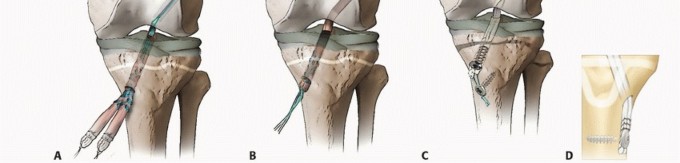

FIG 3 • Algorithm for management of complete ACL injuries in skeletally immature patients.

The approach to ACL reconstruction in the skeletally immature patient should be based on physiologic age and growth remaining. Knee size can also be considered in the feasibility of various techniques (

FIG 3

).

A variety of other physeal-sparing or physeal-respecting hybrid reconstructions have been described and may be used in cases where patients are in between the previously noted categories (

FIG 4

*). One common reconstruction technique is the epiphyseal femoral tunnel combined with the transphyseal tibial tunnel to avoid creating such an oblique femoral tunnel in a younger adolescent with significant growth remaining.

FIG 4 • Examples of repairs in male patients aged 6 to 14 years old. A. Skeletal age 6: combined intra-articular and extra-articular with iliotibial band. B. Skeletal age 8: modified Anderson. C. Skeletal age 10: all-epiphyseal.

*

D. Skeletal age 12: hybrid. E. Skeletal age 14: transphyseal.